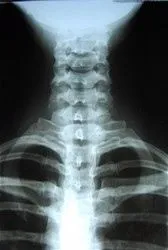

X-Ray

xray.jpg If xray's are neeeded we will send the patient to an x-ray facility for the necessary films. Depending on the findings, we may call for an MRI or other imaging study of the back, or work with your Primary Physician if requested.